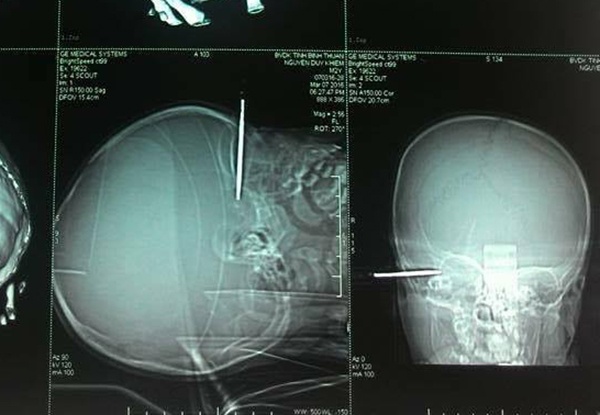

| Chiếc tuốc nơ vít cắm vào thái dương bệnh nhi nhưng chưa gây tổn thương não. Ảnh phim chụp X-quang. |

Phát hiện vụ việc, người thân đưa bé đến bệnh viện cấp cứu trong tình trạng nguy kịch. Các bác sĩ thực hiện xét nghiệm, chụp phim và tổ chức mổ cấp cứu ngay sau đó.